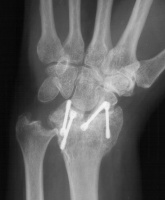

Clinical Example: Radioscapholunate Fusion and Triquetrum excision for Radiocarpal Arthritis

Radioscapholunate fusion is a treatment option for radiocarpal arthritis following distal radius fracture or associated with rheumatoid arthritis. Range of motion is usually less than half of normal following this procedure. Technical modifications to improve range of motion include distal scaphoid excision, or as in this case, triquetrum excision and excision of distal ulnar articular surface to manage ulnolunate abutment. There are a variety of fixation techniques. In this case, crossed Herbert screws were used: dorsal carpal bone to palmar radius and dorsal radius to palmar carpal bone.

Preoperative Xrays:

Three months postop :